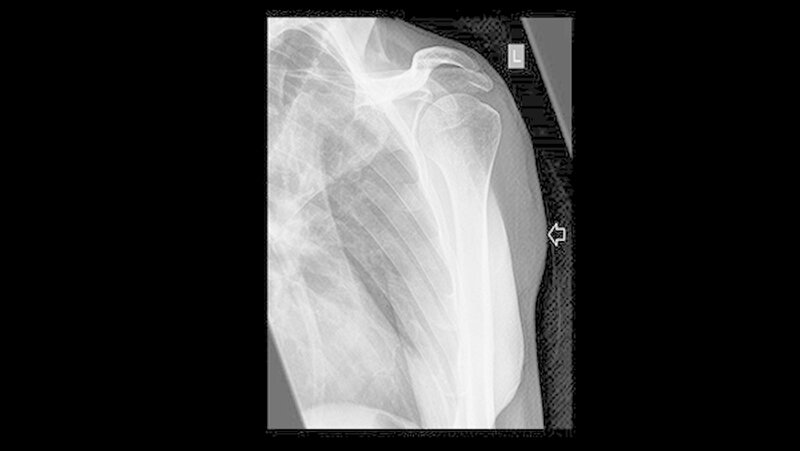

Röntgen und MRT sind nicht eindeutig

Weder das Röntgenbild noch die weitere Untersuchung mit magnetresonanztomografischer Bildgebung gaben eindeutigen Aufschluss. Daraufhin wurde eine Biopsie veranlasst, die die Verdachtsdiagnose einer Metastase des oralen Plattenepithelkarzinoms histologisch bestätigte.